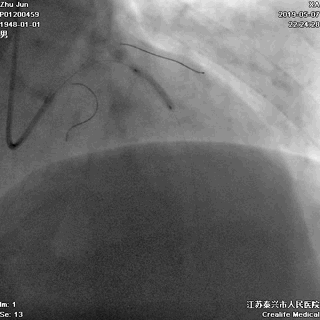

游离一根导丝至升主动脉,防止导管深插

轻轻冒烟,证实指引导管到位

轻轻冒烟,大致了解前降支的情况

这一步相当重要。否则,无论是导管嵌顿,还是导管深插,稍不留意患者都有可能一招致命。